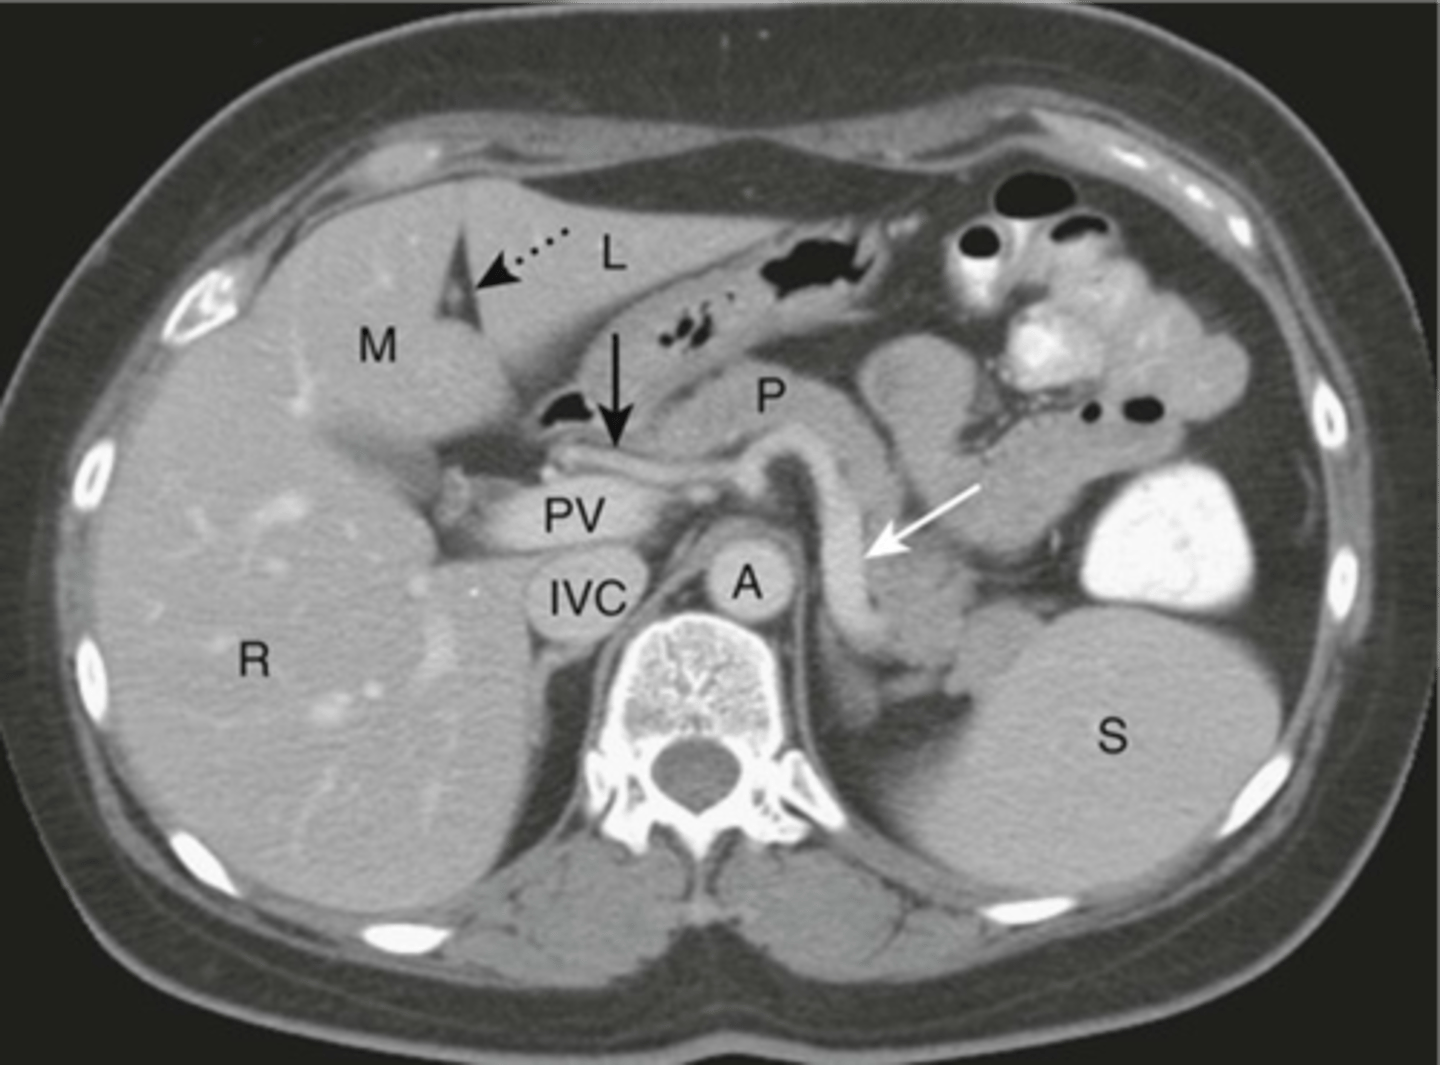

Normal pancreas CT

Normal CT